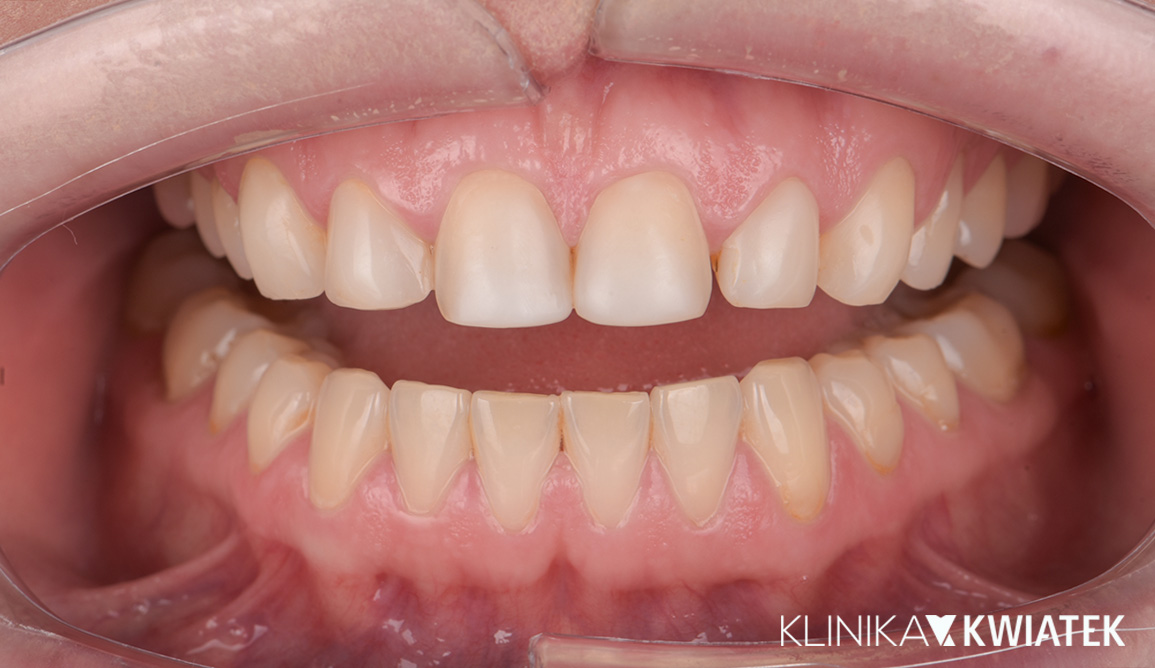

PRZED

PO

Odbudowa estetyczna za pomocą koron, koron na implantach i licówek

Nasza Pacjentka marzyła o harmonijnym, jasnym uśmiechu – bez braków, asymetrii czy kompromisów estetycznych. Po zakończeniu leczenia ortodontycznego zdecydowała się na kompleksową metamorfozę: odbudowę brakujących zębów za pomocą koron na implantach, przeszczep dziąsła (FGG), wybielanie oraz bonding dolnych zębów techniką flow injection.

W trakcie leczenia korzystała także z fizjoterapii stomatologicznej, co pomogło zoptymalizować pracę stawów skroniowo-żuchwowych i mięśni żucia.

Efekt? Spójny, naturalny uśmiech, który nie tylko spełnił jej marzenie, ale też podkreślił rysy twarzy.